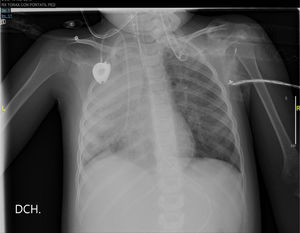

En la radiografía de tórax del día siguiente, presenta una opacificación prácticamente completa del pulmón derecho con infiltrados paracardiacos izquierdos (fig. 2).